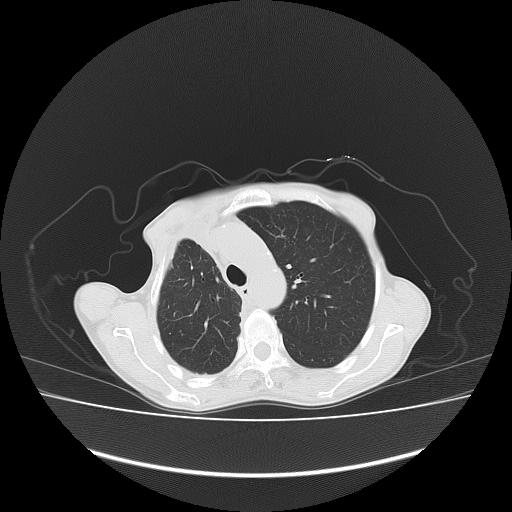

标题: CT16930:女 59 胸痛6个月 胸水脱落细胞学见瘤细胞 [打印本页]

标题: CT16930:女 59 胸痛6个月 胸水脱落细胞学见瘤细胞

可见多发肺内病灶,且胸膜病灶较多有圆球状而非丘状,多考虑胸膜转移瘤伴胸腔积液,右侧胸廓缩小固定,且部分病灶呈丘状,尚不除外恶性胸膜间皮瘤伴肺内转移

右侧胸膜增厚,局部呈结节状增厚,右侧胸腔少量积液。双肺未见确切肿块影。纵隔未见淋巴结肿大。气管、支气管通畅。考虑右侧胸膜间皮瘤(恶性?)可能性大。不除外癌性胸膜炎。

恶性胸膜间皮瘤伴肺内转移可能性大;或胸膜、肺内均为转移瘤,左肺下叶亦见多发小结节影。

右侧胸廓塌陷,右侧胸膜广泛增厚并见多发胸膜结节,右侧少量胸腔积液并包裹。

右侧广泛胸膜增厚,局部呈结节状增厚,右侧胸腔少量积液。双肺未见确切肿块影。纵隔未见淋巴结肿大。气管、支气管通畅。考虑右侧胸膜间皮瘤(恶性?)可能性大。支持!

右胸腔结节均考虑来自胸膜(部分来源于叶裂),考虑胸膜间皮瘤或转移瘤.